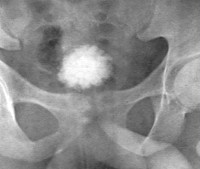

• Ретроградная цистография. Введение рентгеноконтрастного вещества в полость мочевого пузыря во время цистографии позволяет более точно оценить его емкость по объему закапываемого препарата. На рентгенограмме определяются резкое уменьшение размера органа, возможные изменения его формы и расположения, специфические дефекты слизистой оболочки, характерные для туберкулезного процесса, новообразования, камни и признаки воспаления.